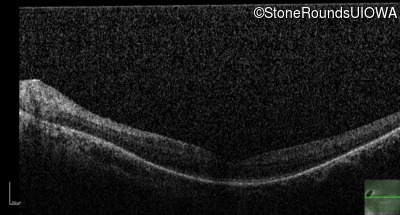

OD

20/70 -2

20/80 -1

OCT Stack